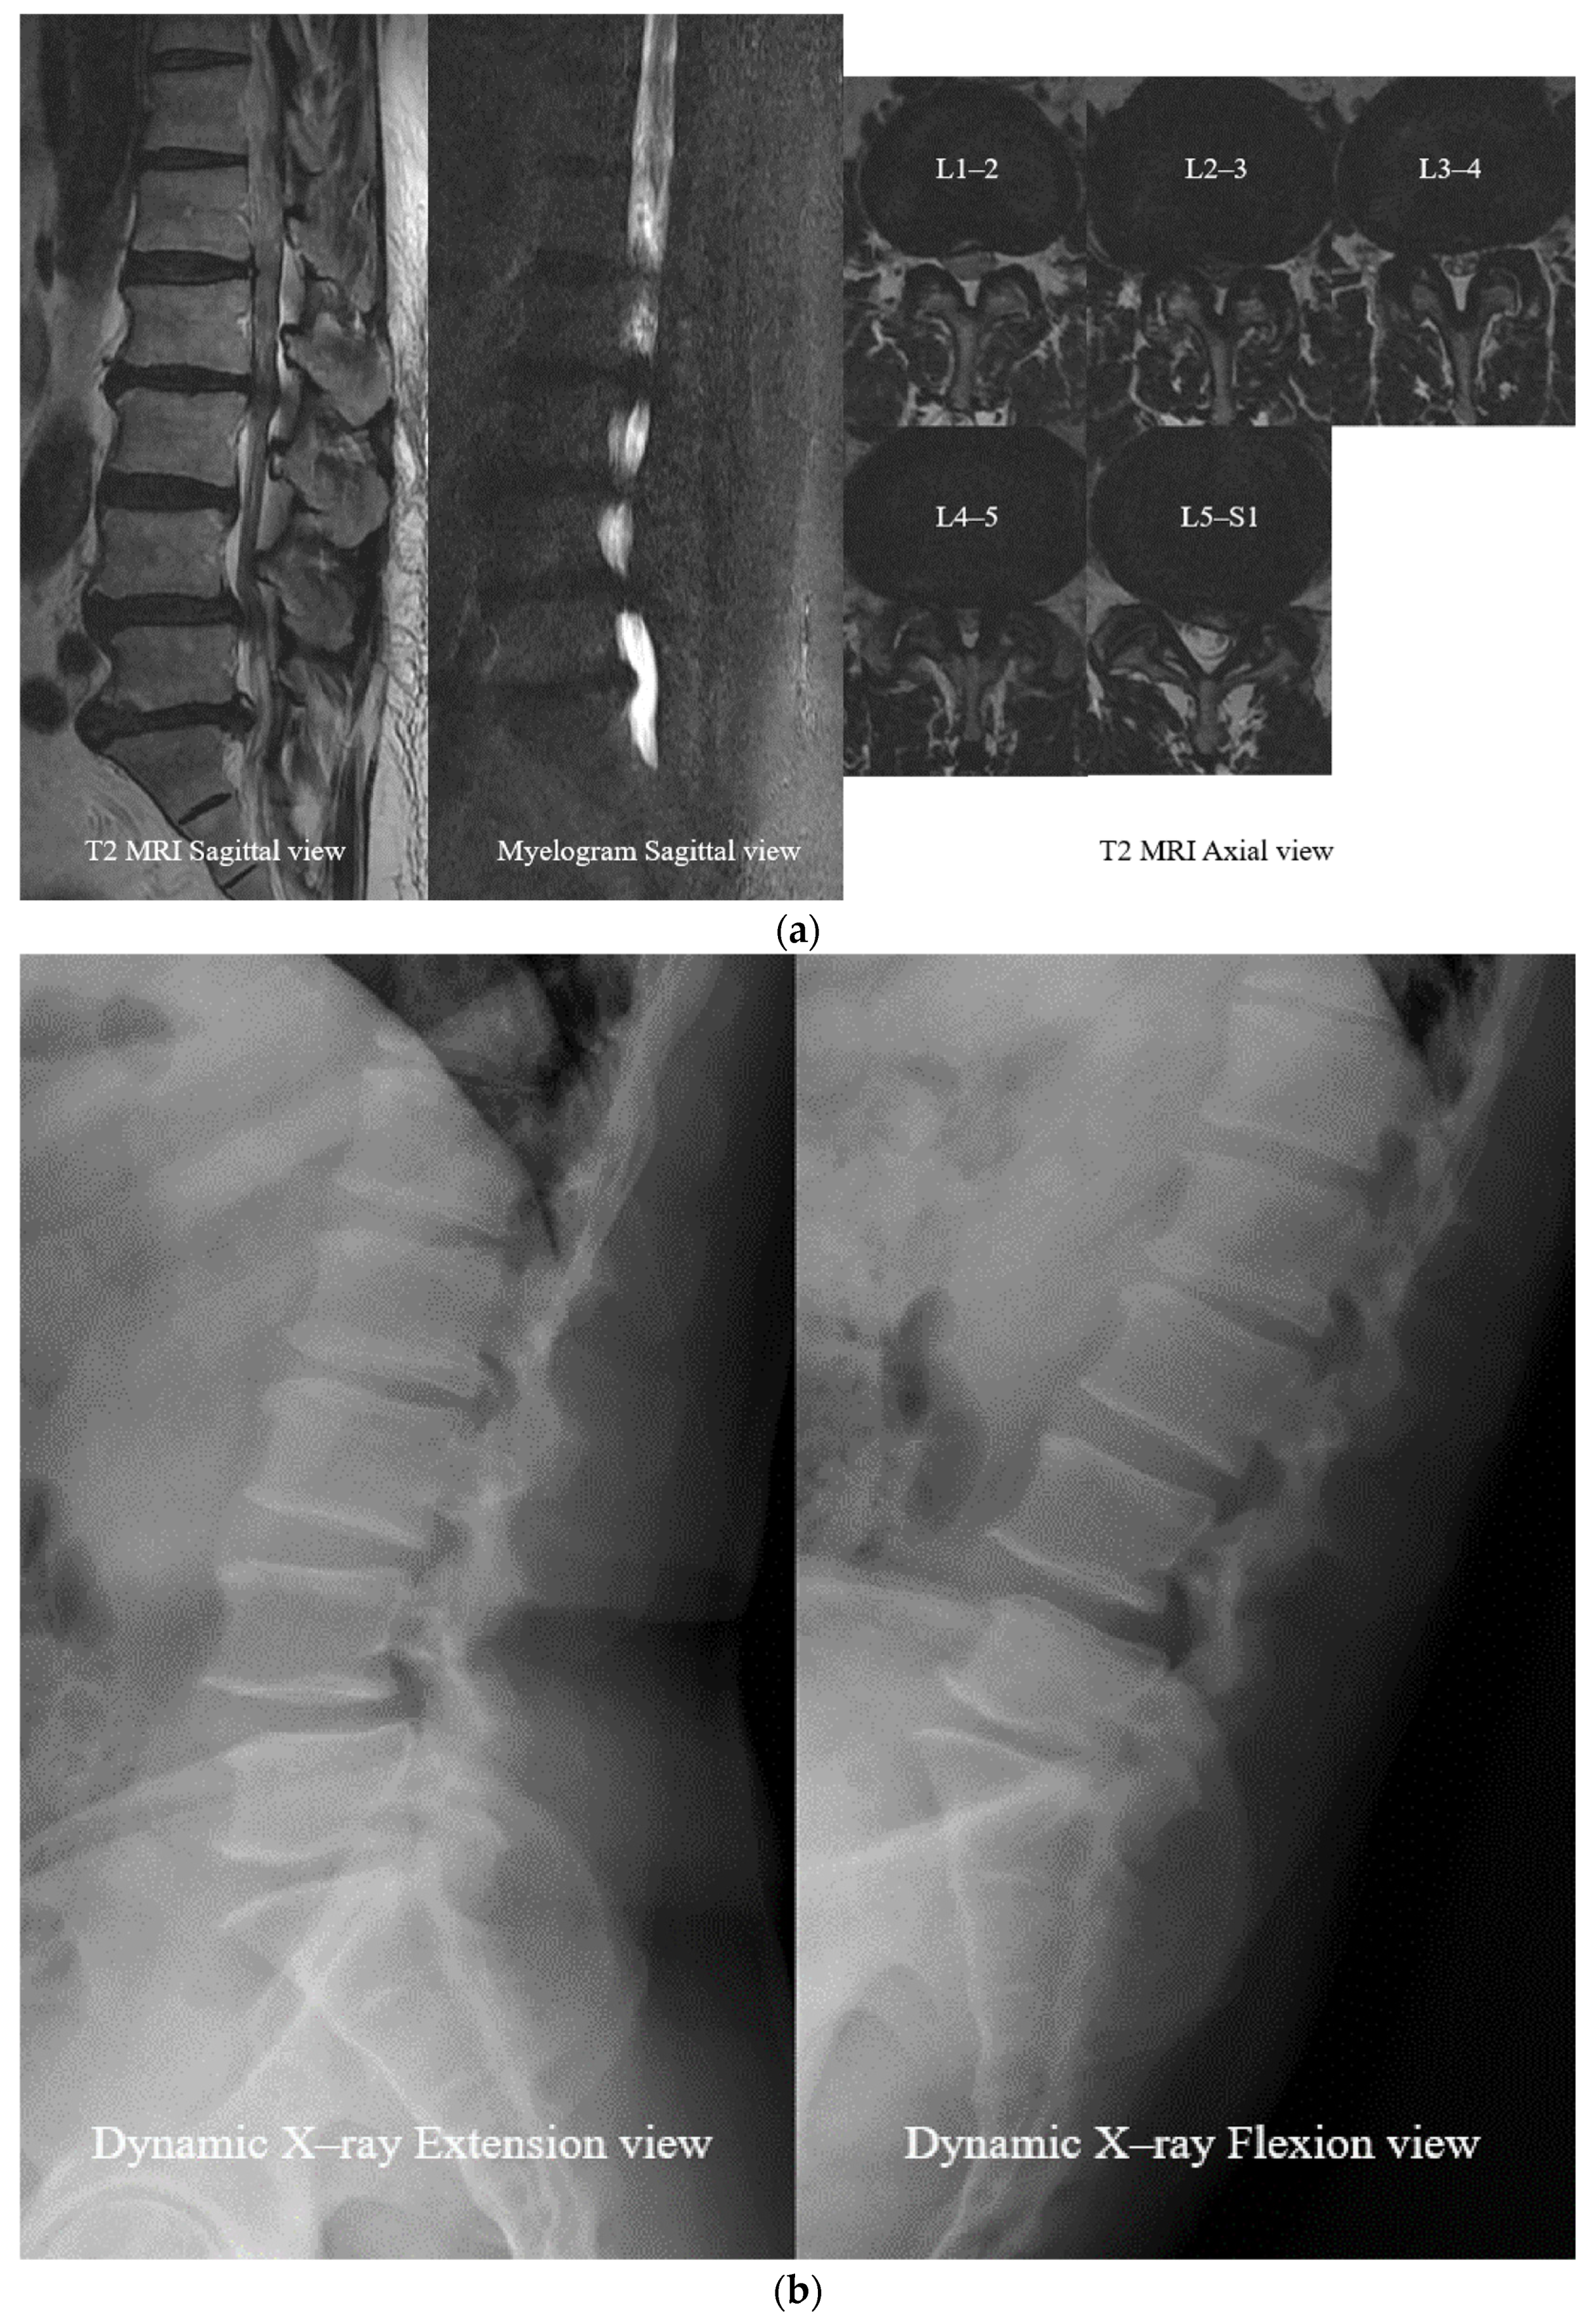

- Open Midline Decompression

- Ligament Reconstruction